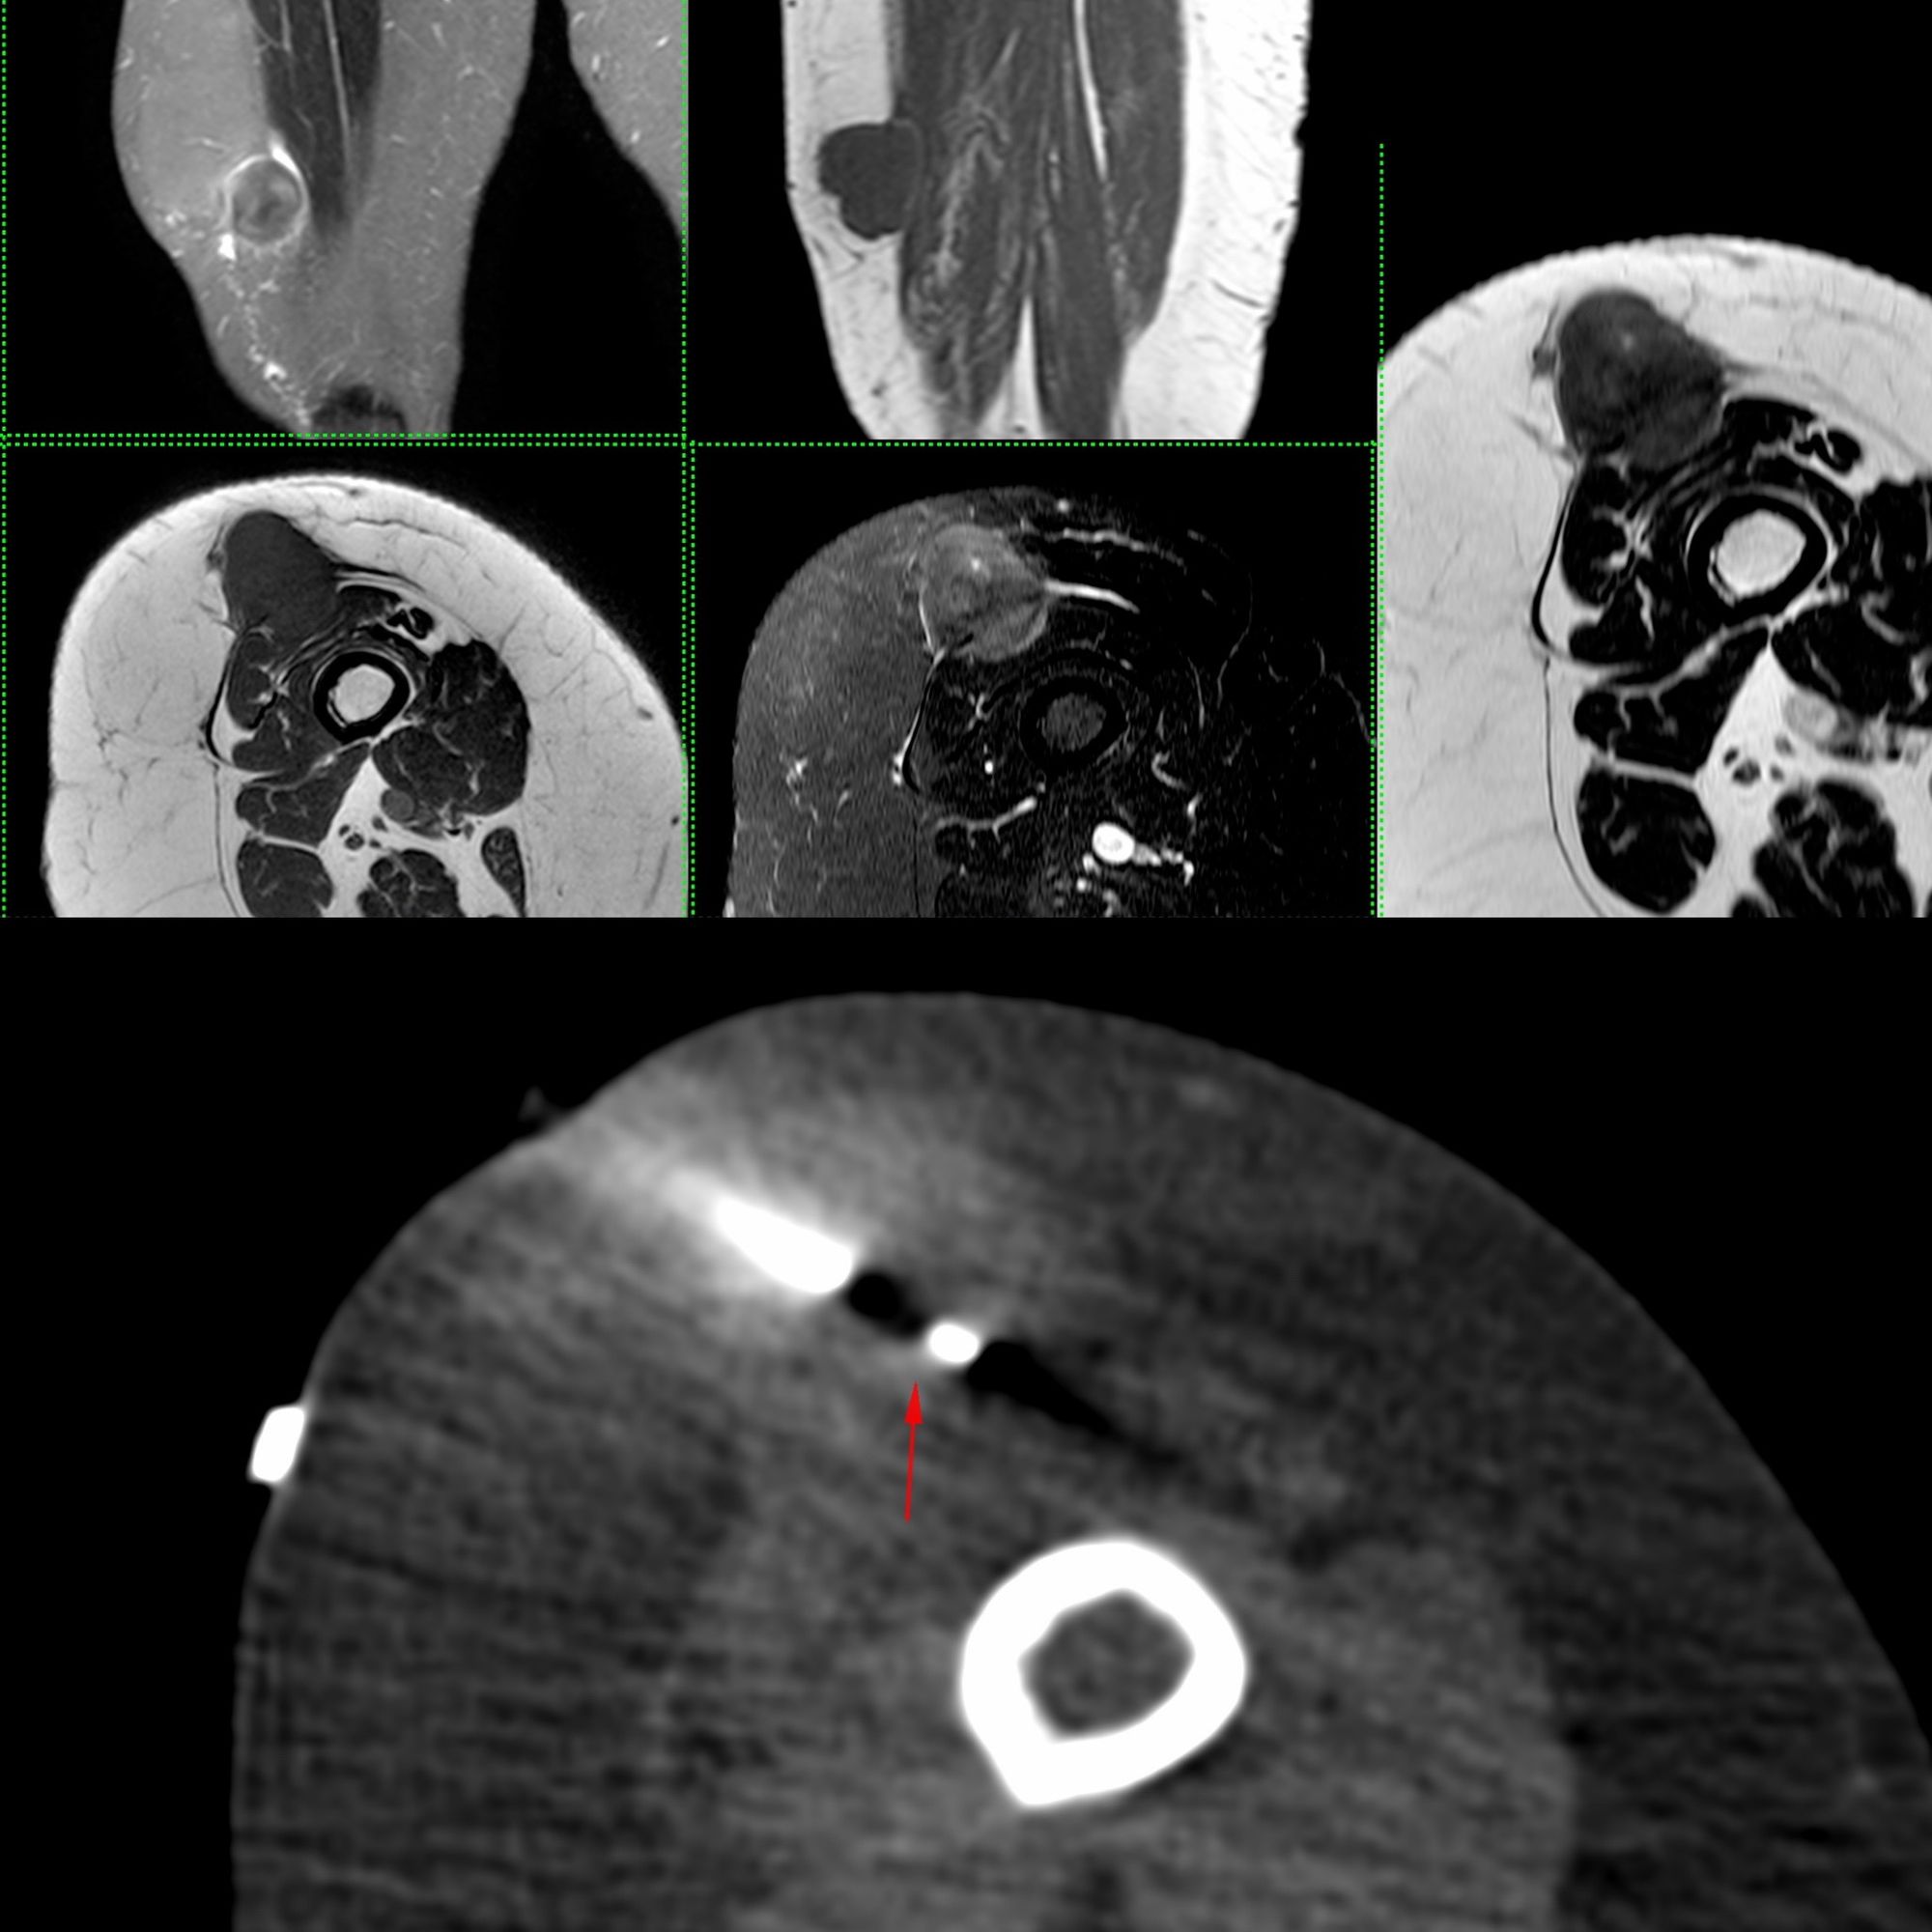

Case 28: Adipocytic Tumor Thigh - High Grade Liposarcoma

Bhavin Jankharia - 30 April 2021